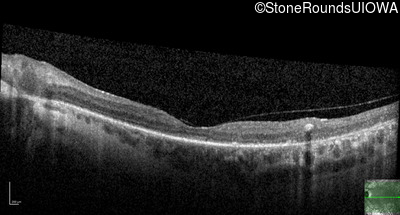

Age at visit: 53 years

This 53 year old woman first noticed night blindness at age 18. More recently she has experienced constriction of her visual fields. She has worn hearing aids since childhood.

Age at visit: 54 years